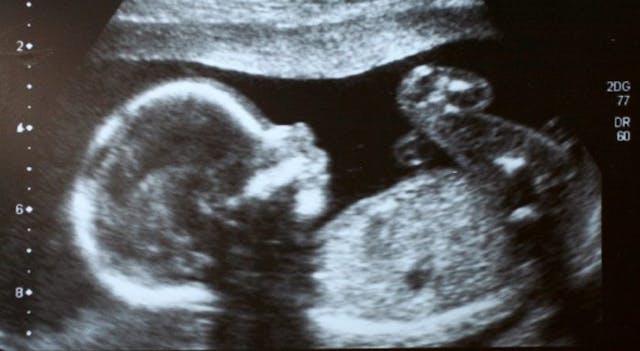

At that first appointment, Reannin watched as her baby’s image was emblazoned on the ultrasound screen.

“It was at that very first ultrasound that I decided I was going to have her,” she said. “The first thing I ever remember seeing was the top of her head. And just like that, I thought, ‘I want her! I’m having this baby. This is going to happen.’”

Her child was small—the same age most babies are when aborted in the U.S.

“She was only 10 weeks old, but she was already this baby—arms, legs, kicking, moving,” Reannin recalled. “And I’ve had four other kids before! But even as a mom of four, I still didn’t even realize the way a baby developed. I couldn’t have told you that was a baby until I saw a Women’s Care Center early ultrasound.”